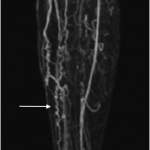

MAGNETIC REASONANCE ANGIOGRAPHY (MRA)

The following gallery shows examples of Buerger disease seen on MRA studies. Click the thumbnails below to open up the gallery.